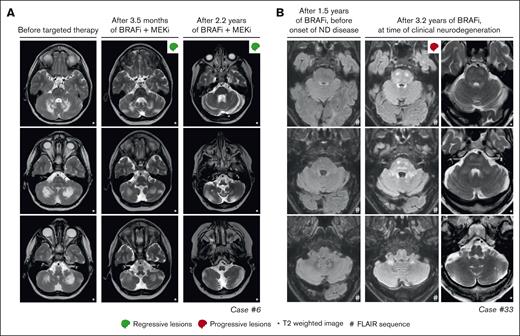

Response and progression of ND lesions. (A) Axial MRI images of case 6, with isolated ND-LCH showing significant reduction in T2-hyperintense lesions after treatment with dabrafenib and trametinib. Note that the remaining hyperintense lesion in the right cerebellum at last follow-up (right column; middle image) is related to the biopsy that was taken from this anatomical site. (B) Axial MRI images of case 33 showing the development of T2- and FLAIR-hyperintense lesions in the pons and cerebellum while receiving treatment with vemurafenib. The patient also developed clinical symptoms of neurodegeneration and died 7.5 months after the MRI scan depicting ND lesions was made. ND, neurodegenerative; FLAIR, fluid-attenuated inversion recovery.

Among the 8 patients receiving targeted therapy for ND-LCH, 2 had a PR of radiologic abnormalities (Figure 5A), 4 had stable lesions, and 2 stopped therapy before response could be evaluated (Figure 2). The 2 patients with a response were treated within 2 years after diagnosis of LCH, whereas the 4 with stable lesions started targeted therapy between 5 and 20 years after diagnosis of LCH. The radiologic response was accompanied by improvement of cognitive symptoms of memory impairment and concentration difficulties in case 10 (who did not have ataxia/dysarthria), whereas repeated neurologic assessments in case 6 showed a rather stable situation, with only slightly improved International Cooperative Ataxia Rating Scale scores (45 to 42).62

In 4 of 27 patients with multisystemic and/or solid lesions, brain lesions characteristic of histiocytosis-associated neurodegeneration were present on MRI at targeted therapy initiation. Only 1 of 4 also had clear neurologic symptoms (patient 32 with dysarthria). During targeted therapy, radiologic response of the brain lesions was noted in case 17 (supplemental Figure 1A), whereas lesions remained stable in 2 of 4 and were not evaluated in case 32, who appeared to have a slight improvement in dysarthria. One of the patients with stable brain lesions during targeted therapy (patient 14 with ECD) had progressive radiologic abnormalities in the pons and cerebellum at 4 and 7 months after stopping vemurafenib because of toxicity (supplemental Figure 1B). This patient did not have progressive neurologic symptoms; therefore, no treatment was initiated. At 2 years after stopping vemurafenib, the patient’s clinical and radiologic situation remained stable. Another patient (case 33 with LCH/ECD) developed new radiologic abnormalities in the pons and cerebellum and clinical symptoms of neurodegeneration after almost 3 years of treatment with vemurafenib (Figure 5B). The patient subsequently received (methyl)prednisolone and increased doses of vemurafenib (up to twice daily 720 mg; 4 out of 6 days), without a clinical response. Eventually, targeted treatment was switched to dabrafenib, but the patient requested euthanasia a few weeks later and died shortly thereafter.